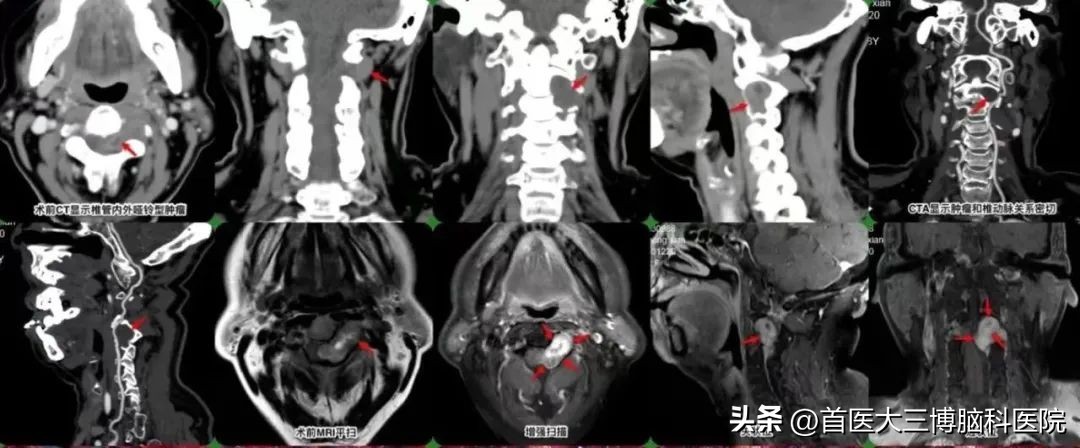

入院后,张永力院长经过详细的查体,并结合影像学检查结果, 初步诊断为:颈2-3左侧硬脊膜外肿瘤,考虑为神经鞘瘤 ,症状明显,有明确手术指征,建议手术。

术前检查

张永力院长介绍:“ 这是一个典型的椎管内占位患者,主要症状就是颈肩部疼痛,麻木,同时肿瘤生长已经造成了颈部相邻脊髓受压损伤,如果肿瘤继续增大,可能进一步压迫脊髓致完全瘫痪,应尽快手术治疗, 这个 神经鞘瘤完全在左侧硬膜外 ,采用半椎板切除既能够 满足手术切除显露的要求,又能保证颈椎的稳定性,还免除了内固定带来的颈部活动受限和医疗费用增加给患者带来的经济负担,可谓一举多得的最佳手术方式 。”